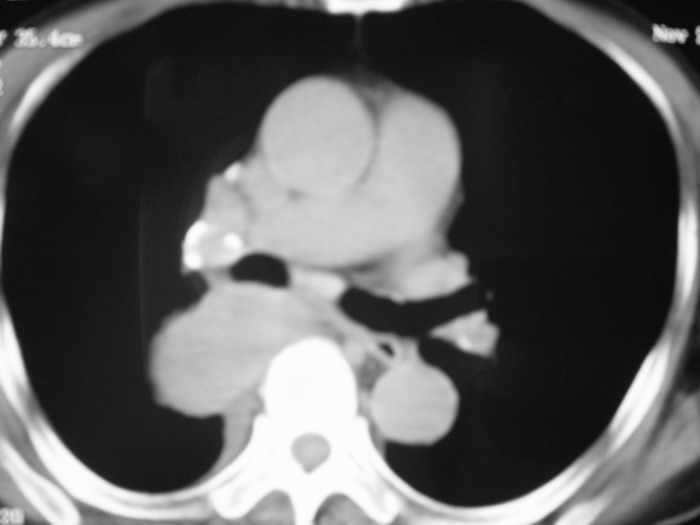

m、70y,反复咳嗽2月。请各位同仁给定位1、(肺?,纵隔?)2、定性。感谢!!

右后纵隔良性占位性病变,神经原性肿瘤可能性大,就其形态看,高密度囊肿待排,建议mri检查。

右下肺纵隔旁较大 均匀密度肿块,部分边缘植入纵隔,气管明显受压 变形。支持:后纵隔肿瘤!首选:神经源性!不支持肺内肿瘤原因:1 肿瘤位于下叶支气管及背段支气管开口区,但未侵犯支气管,只是受压表现。2 纵隔内未见肿大淋巴结。3 肺内未见阻塞性肺炎。

考虑右后纵隔良性肿瘤,以神经源性肿瘤可能性大。增强一下也能解决问题;神经源性肿瘤有明显强化。